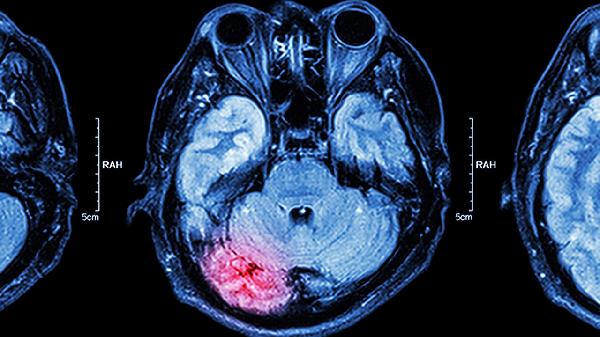

3、出血倾向

血小板极度减少导致皮肤瘀斑、鼻衄、消化道出血甚至颅内出血,需输注血小板及使用止血药物如氨甲环酸。